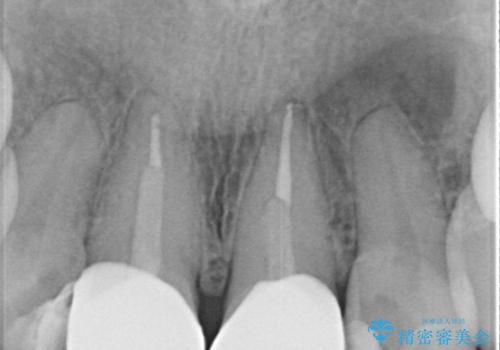

- [前歯の色が気になる」を主訴に来院された患者様です。歯の形を整えた後オールセラミッククラウンで治療を行いました。

以前他院にてセラミッククラウンを被せていたのですが、セメントの劣化なのか色が青白くなっていました。

歯の形を整えた後、色が透けないよう処置をしてオールセラミッククラウンで治療を行いました。